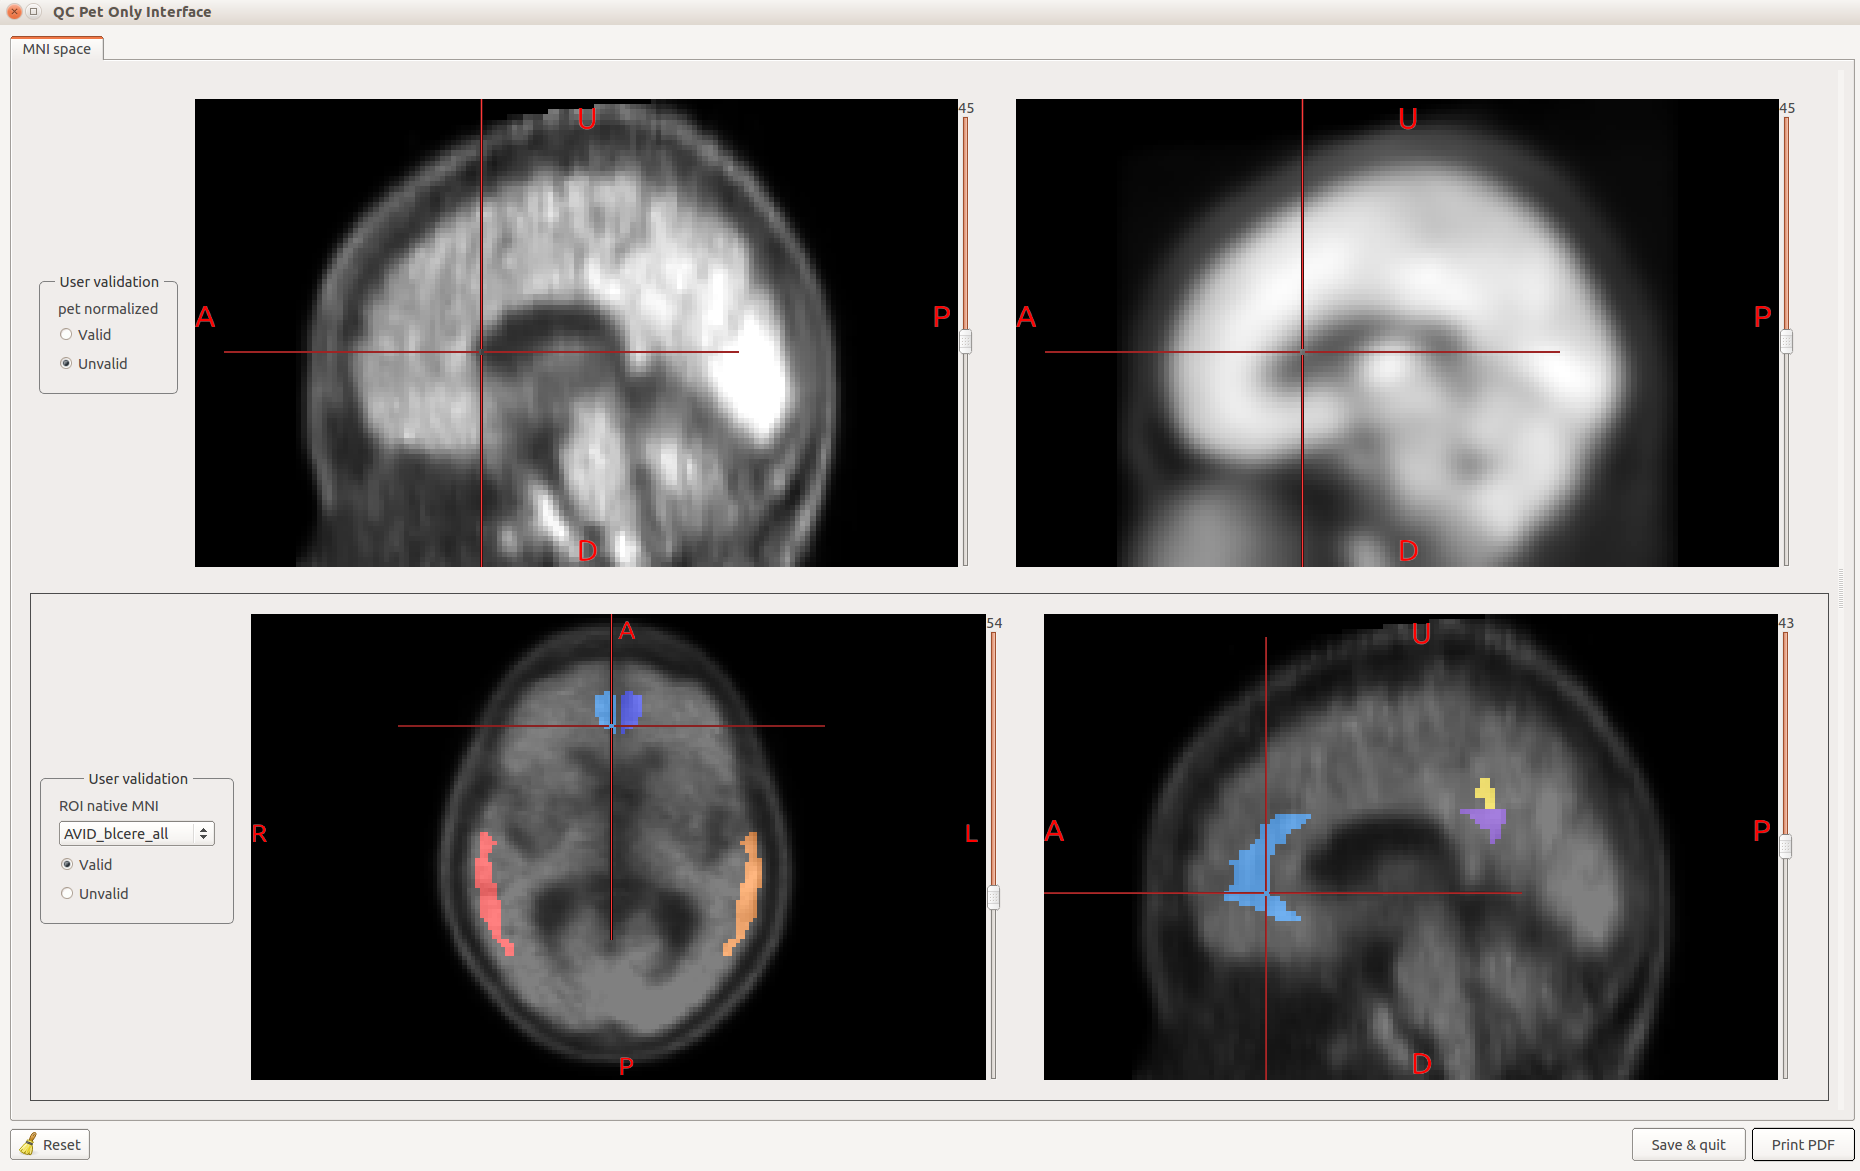

Nuclear imaging toolbox

A toolbox for BrainVISA developed by the |cati_logo| CATI project labs